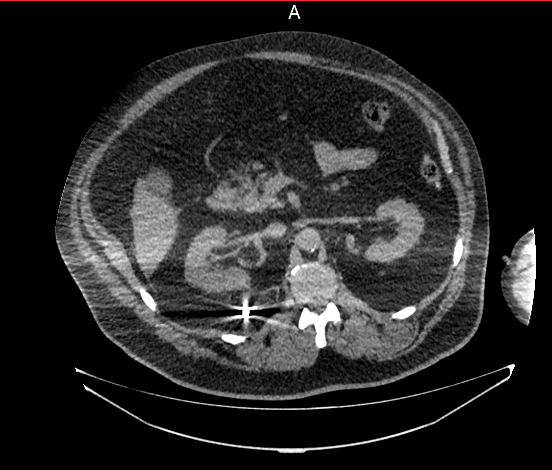

Компьютерная томография.

Позволяет достоверно выявить инородное тело в анатомически сложной области, оценить степень изменений в окружающих тканях, взаимоотношение инородного тела с прилежащими органами, а также выявить наличие возможных осложнений.

Метод выбора для выявления госсипибомы - КТ. В раннем послеоперационном периоде госсипибома наиболее достоверно диагностируется при визуализации округлого образования с губчатой внутренней структурой, с множественными пузырьками газа в структуре. При в/в контрастировании визуализируется тонкое периферическое кольцо контрастного усиления, соответствующее гранулематозному воспалению вокруг инородного тела. В позднем послеоперационном периоде госсипибома может утратить губчатую структуру и КТ-картина может быть сходна с ограниченным скоплением жидкости или с абсцессом. В отдаленном послеоперационном периоде госсипибому следует дифференцировать с новообразованиями, при этом отмечается отсутствие достоверного накопления контрастного вещества как в центральной зоне, так и стенке госсипибомы. В позднем и отдалённом постоперационном периоде также возможна кальцификация стенок госсипибомы.